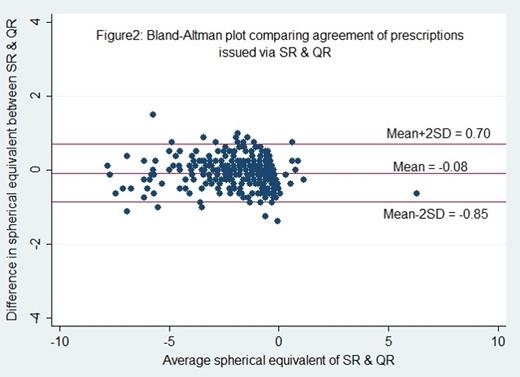

Purpose : In low-resource settings with large burden of uncorrected refractive errors, auto-refractors are conventionally considered too expensive and inaccurate to significantly improve refractive eye care. We compared patient acceptance of eyeglasses prescribed using a low-cost, portable auto-refractor (the QuickSee) with that of eyeglasses prescribed via standard subjective refraction. We also compared the accuracy of the QuickSee refraction measurements with subjective refraction performed by trained technicians at Aravind Eye Hospital (AEH), India. |